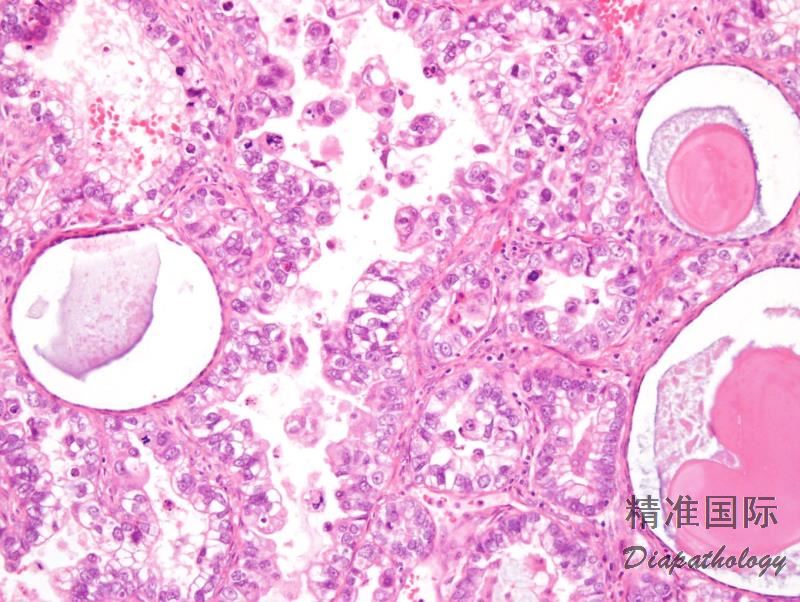

由胞浆透亮或嗜酸性,最少局部具有高级别核的多角形或鞋钉样细胞呈实性、乳头状或管状排列的肿瘤,属于 II 型子宫内膜癌。

肿瘤呈实性、乳头状、管状和囊状结构,各种结构比例变化很大,可以以一种结构为主;

实性结构常由大量透明细胞混杂嗜酸性细胞组成,而乳头状、管状和囊状结构主要由鞋钉样细胞组成(核大,突出于腺腔),其间散在透明和嗜酸性细胞;囊状结构常衬覆扁平细胞;

细胞异型性、多形性不一致,但最少有部分细胞为高级别核,表现为细胞核大,明显多形性,多数病例核分裂像多见,并可见病理性核分裂像;

近 2/3 病例可见 PAS 阳性且耐淀粉酶消化的细胞内和细胞间透明小体,类似于卵黄囊瘤中的透明小体;

肿瘤内乳头状区域可有砂粒体。